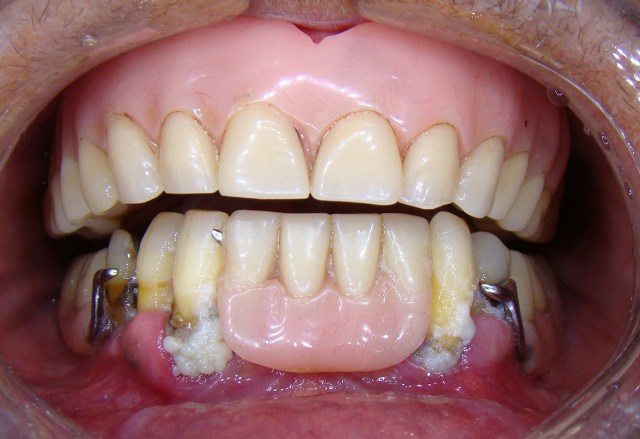

Paciente apresentava alguns dentes inferiores e utilizada uma prótese parcial remov&iacut...